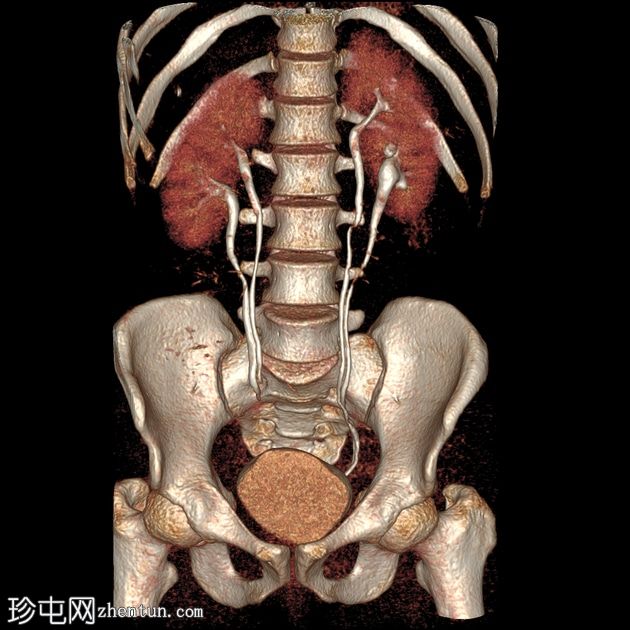

最大强度投影 (MIP)

三维容积

10.jpg

渲染

11.jpg

12.jpg

CT肾血管造影显示一条起源于左肾下段的副肾静脉,该静脉环绕主动脉走行,并接受来自腰静脉的属支,走行于主动脉后方,最终汇入下腔静脉。

双侧肾脏集合系统重复,分为上极和下极两部分。右侧输尿管在中段汇合,而左侧输尿管在进入膀胱前仍部分分离,符合双侧部分输尿管重复畸形(双分输尿管)。

本病例展示了一条环绕主动脉的副左肾静脉,其走行于主动脉后方并汇入下腔静脉,而右肾静脉解剖结构正常。

双侧肾动脉解剖结构正常,双侧肾动脉均起源于L2椎体水平的腹主动脉,管径正常,无狭窄、动脉瘤、夹层或副动脉。

双侧重复肾盂输尿管系统,上下极部分明显。右侧重复的输尿管在中段汇合,而左侧输尿管在进入膀胱前仍部分分离,符合双侧部分输尿管重复畸形(双分输尿管)。双肾大小、位置、轮廓和实质厚度均正常,造影剂浓度和排泄功能正常。未见肾结石、肾积水或局灶性肾脏病变。